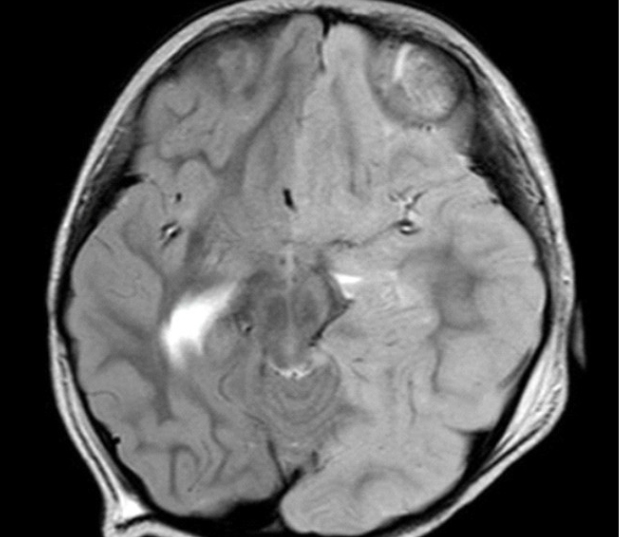

| Hình ảnh MRI chuỗi xung T2W của bệnh nhân N.H.X (ảnh: BVCC) |

Trường hợp thứ hai là bé gái N.H.X (3 tuổi, ngụ tại TPHCM) nhập viện sau 1 ngày sốt cao và lên cơn co giật kéo dài khoảng 30 phút. Sau khi nhập viện, trẻ tiếp tục bị co giật toàn thân nhiều lần xen kẽ co giật miệng và tay phải. Sau co giật, bệnh nhi rơi vào tình trạng hôn mê, suy hô hấp phải hỗ trợ thở máy.

Khai thác bệnh sử của bác sĩ từ người nhà ghi nhận, trẻ có tiền căn động kinh từ lúc 14 tháng tuổi. “Kết quả MRI sọ não cho thấy bệnh nhi có tổn thương kèm phù não toàn bộ nửa bán cầu trái, đẩy lệch đường giữa sang phải, bán cầu não phải bị ép xẹp. Chúng tôi đã hội chẩn và quyết định sử dụng steroid liều cao cùng kháng thể Globulin cho trẻ” - BS Việt chia sẻ.